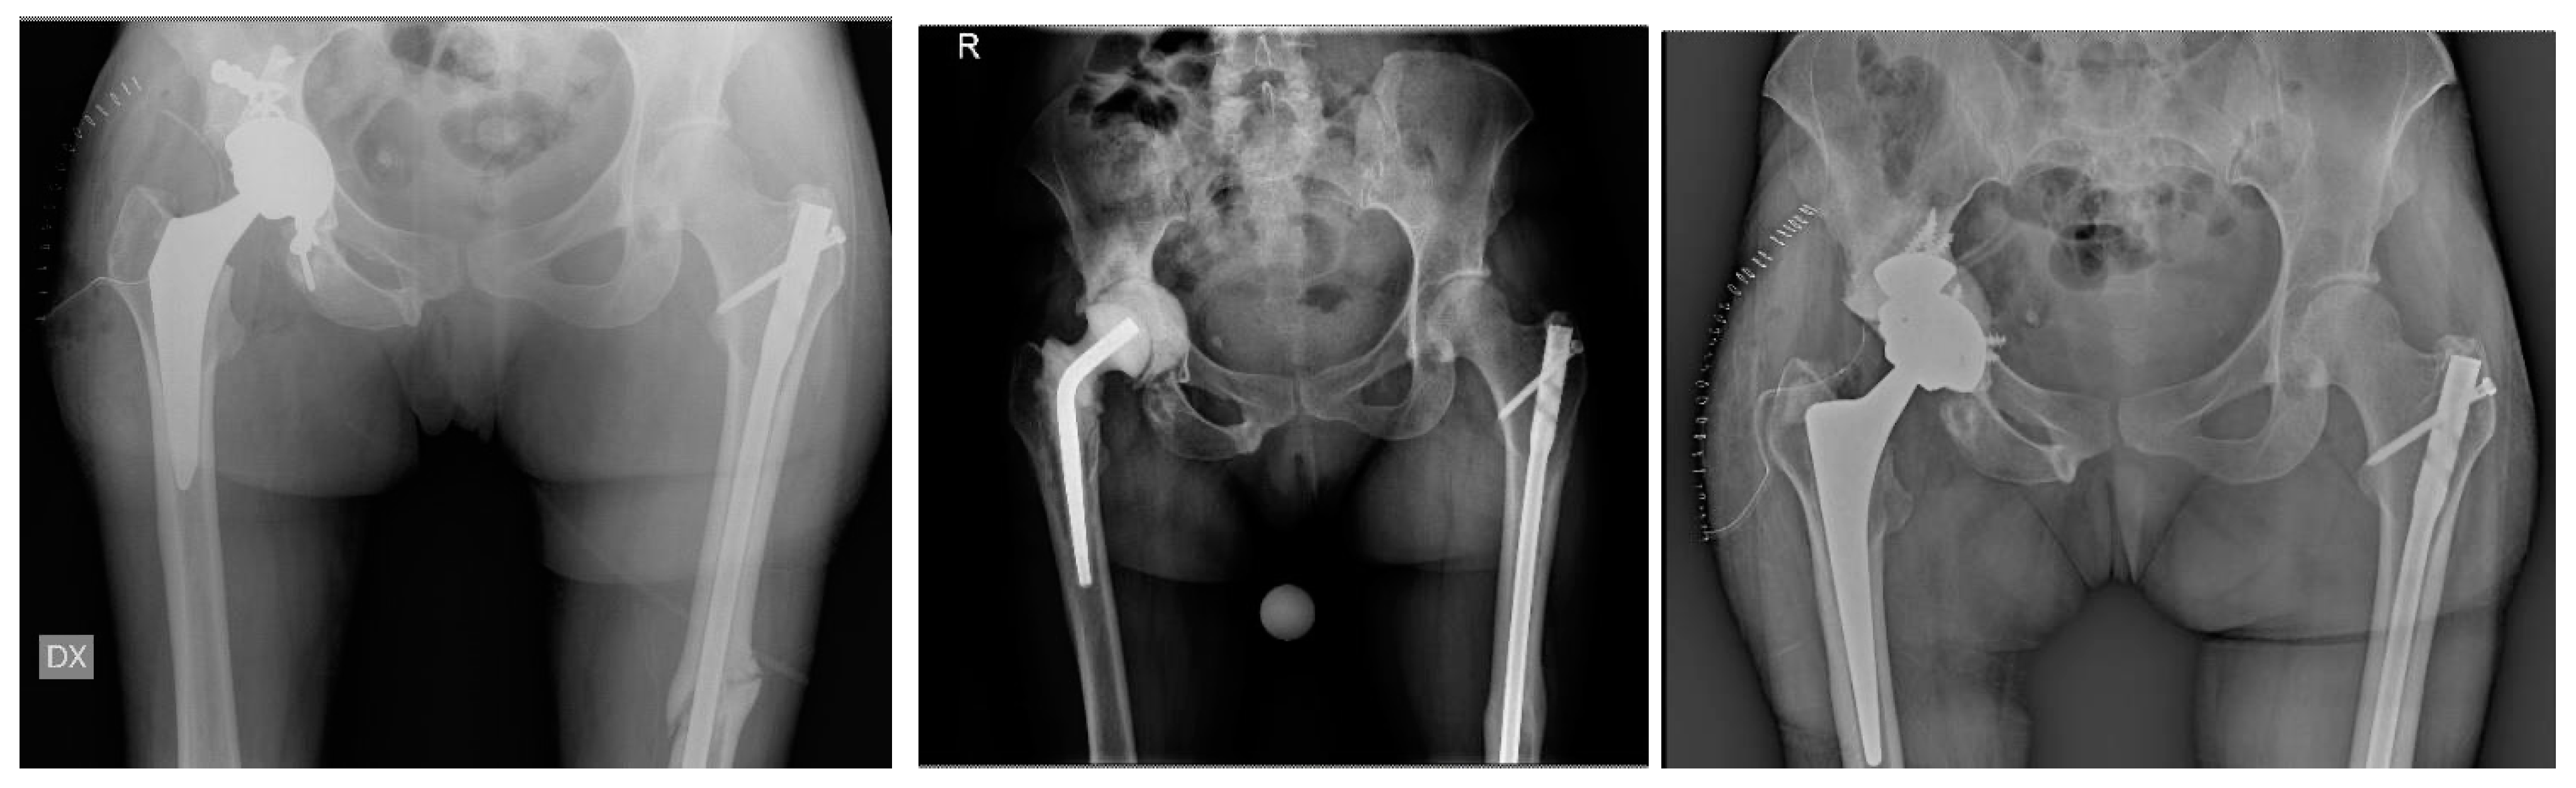

Revision of Failed Short Stems in Total Hip Arthroplasty

2.2. Surgical Technique